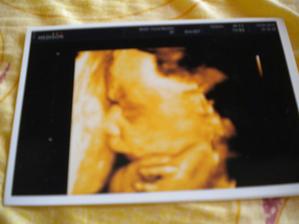

24.5. jsem byla s miminem na NT Screeningu a má 4 končetiny, nosní kůstku a šíjové projasnění 1,1mm - takže vše vypadá v pořádku. Ještě uvidíme jak dopadnou odběry, ať můžem být v klidu úplně 😉 Od sestřičky jsem dostala průkazku pro těhotné paní 😉 a od pana Dr. hezkou fotečku mimina v břiše 😉

14.9. Kontrola opět i s fotečkou. Jáchym váží už cca 1100g a já přibrala od začátku těhotnění 7 kilo. A přes břicho mám 98 cm 😲 (kam toto povede?!? ;DD)

11.10. mi Jáchyma prohlížela paní Dr. zaskakující za toho mého. Ukázala mi ledviny, žaludek, plný močák i pracující srdíčko 😉 Taky zkontrolovala rtíky, které měl Jáchym hezky našpulené a žádný rozštěp tam není 😉 Jen nemáme fotečku, páč paní Dr. neumí s 3D UTZ.